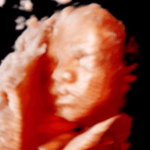

3D

Je baby in stilstaande beelden met perspectief en kleur. Een 3D echo is een stilstaand beeld van een levensechte weergave van jouw kindje. Hierbij zijn duidelijke contouren zichtbaar van bijvoorbeeld de vingertjes, het neusje en de lipjes.